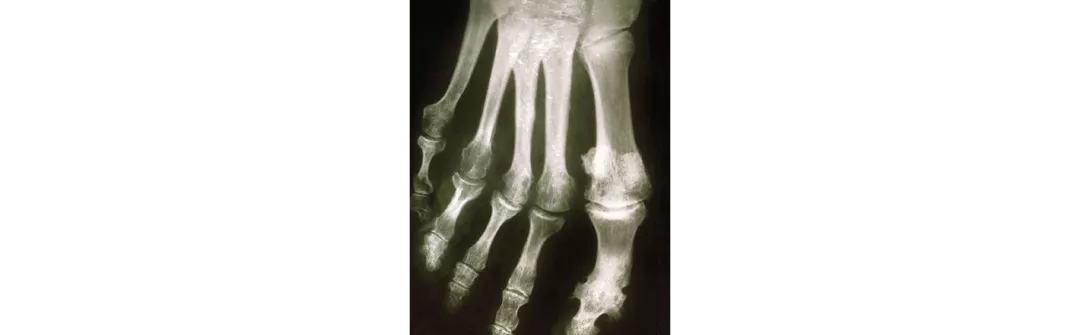

En cas d’arthrite psoriasique, on observe des modifications typiques sur les radiographies:2

érosions articulaires

rétrécissement de l’interligne articulaire

ostéoprolifération

ostéolyse (p. ex. aspect en cupule)

acro-ostéolyse, ankylose

formation d’épines

spondylite

Les signes radiologiques se distinguent nettement de ceux de la polyarthrite rhumatoïde.2

Modifications radiologiques typiques dans le cadre de l’arthrite psoriasique 4

Atteinte articulaire périphérique:

Atteinte des articulations IPD

Erosion asymétrique des articulations IPD/ atteinte des articulations IPP (en saucisse)

Survenue concomitante de manifestations radiologiques ostéolytiques et ostéoprolifératives

Ostéolyses marquées et en longueur (aspect en cupule, doigts/ orteils en lorgnette)

Tendance à l’ankylose

Périostite des régions osseuses extra-articulaires

Enthésite calcifiante

IPD = (articulation) interphalangienne distale; IPP = (articulation) interphalangienne proximale